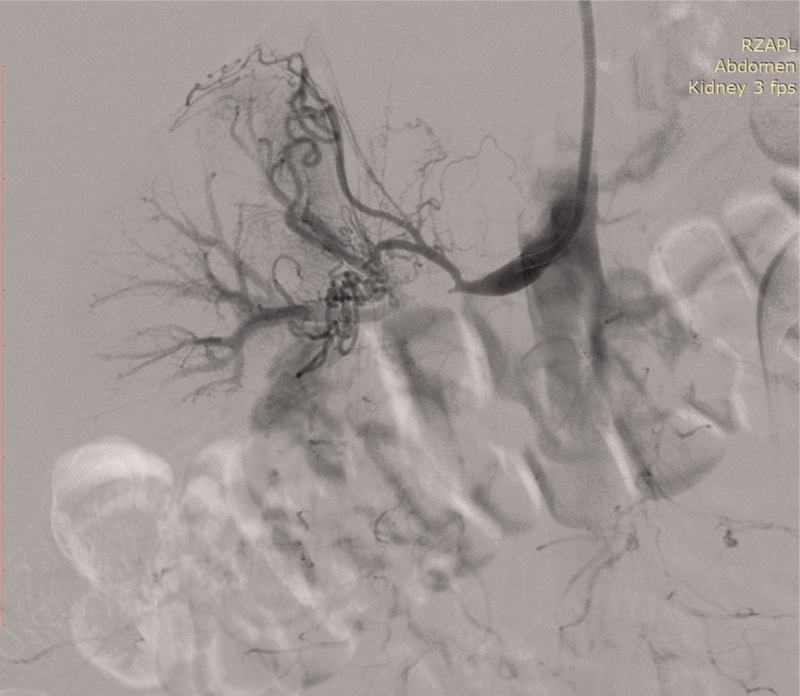

Abstract Image